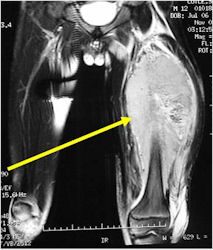

- Soft Tissue Mass in 90% of of cases

- Distant metastases (predominantly in lungs and other bones)

- Ewing sarcoma responds well to chemotherapy. Often there is a dramatic reduction in size of the tumor.

- Lesions grossly confined to bone have a better prognosis than those with a soft tissue component